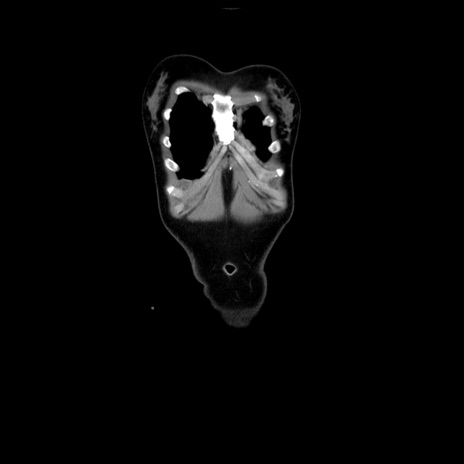

症例39(冠状断像)

【症例】40歳代女性

【主訴】上下腹部痛

【現病歴】2日目から下腹部痛あり。夜間は痛みで眠れなかった。昨日より上腹部痛と下痢が出現。臥位で痛みは軽快したため、休んでいた。本日になって臥位でも立位でも痛みが強くなってきたため救急要請。

【既往歴】子宮内膜症

【身体所見】部:平坦・軟、左上下腹部に圧痛あり、反跳痛あり。

【データ】WBC 21800、CRP 26.78

CT